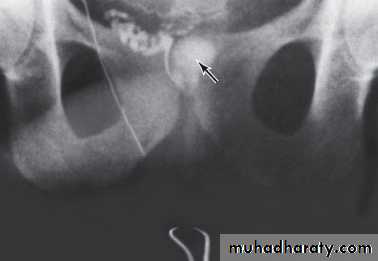

VasographyUsed to assess the patency of the vas, seminal vesicles & ejaculatory duct & to aspirate vasal fluid.

The best timing of it is prior to vasal reconstructive surgery.

Indicated in :

• Azospermia with normal testicular biopsy.

• Severe oligospermia